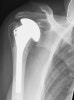

4조각 골절은 상완골두로 혈류장애를 동반하므로 골절 내고정 수술보다는 몸쪽 상완골의 전치수술을 필요로 합니다.

Neer prosthesis